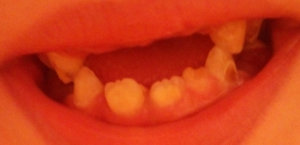

У нашей 5-летней дочери на нижней челюсти в районе центральных резцов с внутренней стороны видно, видимо, прорезывание постоянных резцов, небольшая припухлость. Резцы немного шатаются.

Нормально ли это? Я думал, что режущий край должен упереться в корень молочного и его вытолкнуть. А режущий край постоянного резца отстает во внутрь на несколько миллиметров.

В идеале они должны, как Вы выразились, вытолкнуть молочные зубы и встать на их место, но все не так просто, как кажется. Необходимо обратится к ортодонту, скорее всего придется удалить молочные зубы, чтобы освободить место для правильного прорезывания зубов.